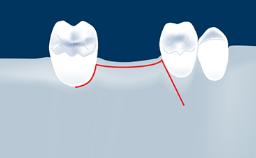

• list the indications for the lateral SFE technique

• describe the surgical treatment concept and steps for the lateral SFE technique and assess the prognosis of this procedure